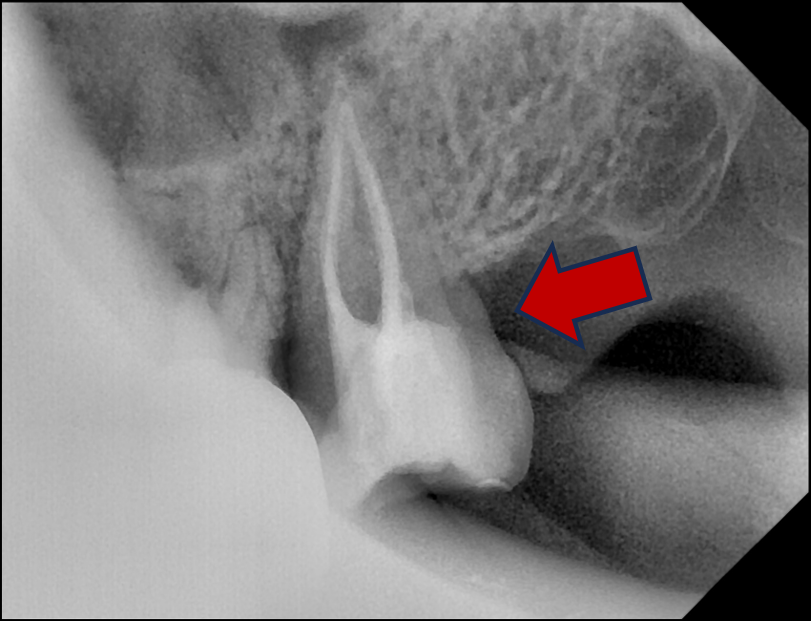

뿌리쪽은 어떤지 CT를 찍어본다.

원래 CT에서는 금속 주변이 하얗게 번져서 잘 안 보이는데,

이 치아는 아래가 워낙 심하게 썩어서 CT에서도 크라운 아래 충치가 확인된다.

심한 통증을 유발한 어금니의 크라운 아래 충치가 CT로 확인된다

하얀색 = 크라운, 검은색 = 충치

뿌리끝에도 염증이 확인되었는데,

크라운 아래 2차충치로 뿌리에 염증이 생긴 CT 사진

상악동에도 심한 염증이 보인다.

크라운 아래 2차충치로 뿌리염증과 상악동염증이 생긴 CT 사진

원래는 공기가 차 있어서 완전한 검은색이어야 하는 상악동이 회색으로 채워져있다.

#27 치아의 뿌리염증이 원인인 듯하다.